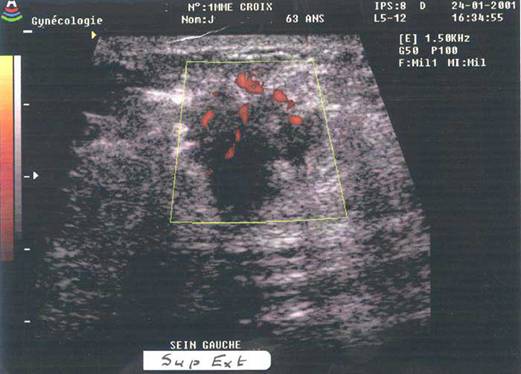

De mai mult de 10 ani, numerosi autori au tentat definirea criteriilor unui flux arterial tumoral pe baza unei analize prin efect Doppler continuu si ecografie duplex. Mai recent, dupa 1987, aparatele de codaj color al fluxului sanguin, au permis studiul, de o maniera mai precisa, al vascularizatiei din leziunile sanului. Cele mai multe studii din zilele noastre au incercat sa stabileasca o relatie intre aspectul caracteristic al fluxului sanguin tumoral si o leziune suspecta clinic sau mamografic. Tipic, un ' flux tumoral ' are o componenta sistolica ridicata si un flux diastolic net marcat corespunzand unei artere cu rezistenta scazuta.

Primele lucrari cu ajutorul Dopplerului continuu au demonstrat asocierea unui astfel de flux la leziunile maligne. Analiza fluxului se poate dirija spre arterele peri sau intratumorale. Trebuie remarcat insa ca prezenta unui flux de slaba rezistenta nu este neaparat specific unei leziuni maligne. Un ' flux tumoral ' se intalneste si in diverse stadii fiziologice ale sanului. In plus, in unele tumori maligne ale sanului vasele sunt putin aparente si chiar absente in tumora sau la periferia sa, deci aceste cancere nu au flux tumoral si nici arborescenta vasculara decelabila.

Demonstrarea arterelor de neoformatie, multe penetrand leziunea focala, este un alt criteriu in favoarea malignitatii.